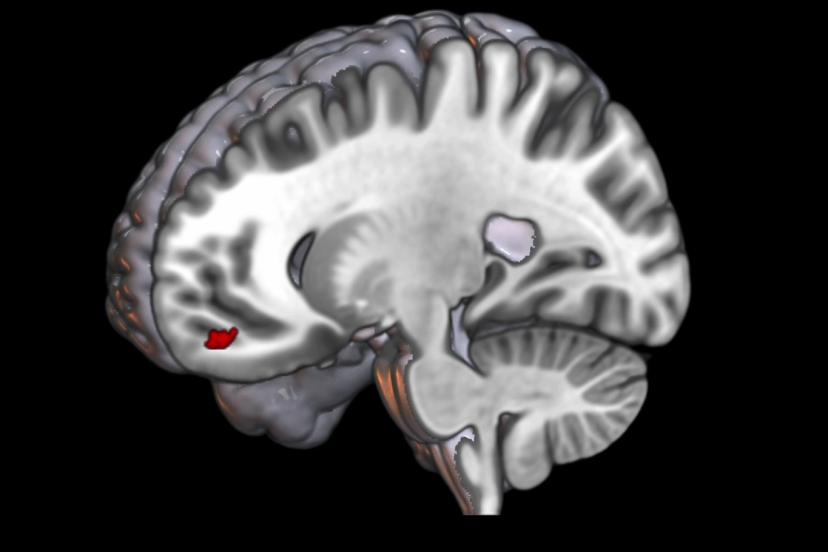

“Normal insan beyninde tekrarlayan uyarı geldiğinde beyin buna verdiği tepkiyi azaltıyor. Ama migrenli beyin aksine tepkiyi giderek arttırmaya başlıyor.” diyen Prof. Dr. Belen, bu artışın, görsel işlemenin yapıldığı beynin arka kısmında değil aksine beynin en ön kısmında bulunan ve üst düzey kontrol merkezi olan orbitofrontal bölgede gerçekleşmesinin son derece önemli olduğunu ifade etti. Belen, “Burası görmenin üst düzey kontrol merkezi ve aynı zamanda da gelen uyarıya zararlı, faydalı ya da duygusal bir değer biçen yer.” dedi.

“Sorun, tekrarlayan uyarıların gereksiz ya da önemsiz olan uyarıyı filtreleme sisteminde bir problem gibi görünüyor ve de ilk kez beynin ön kısmında da bununla ilgili bir yerin yer aldığını görüyoruz. Bunu biz kanıtladık.”

Doktora sonrası araştırmacı Dr. İlkem Güzel de “Alt düzey görsel işlemleme bölgelerinin doğrudan ağrı bölgesiyle ilişki halinde olduğunu tespit ettik. Bu tespit bize migren hastalarında ışıktan rahatsız olma durumunu açıklama fırsatı sundu.” dedi.